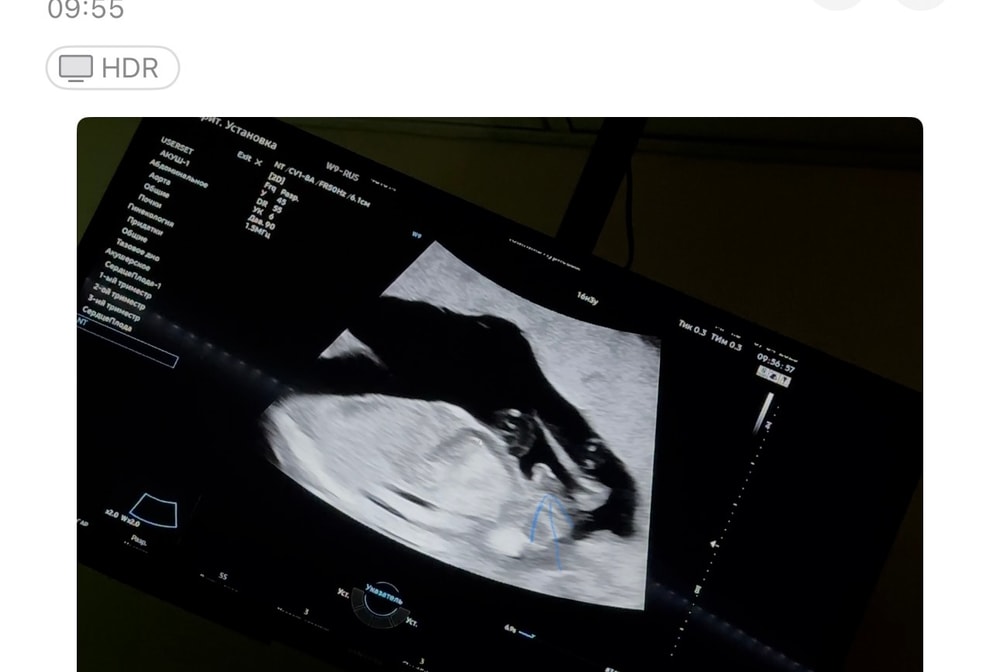

На первом скрининге в 12н 6д в конвертик написали, но врач прям сказала что это не 100%. Сегодня на узи ходила, подтвердили пол, прям видно 😁 Изображение Изображение А тут стрелочкой показывала мужу